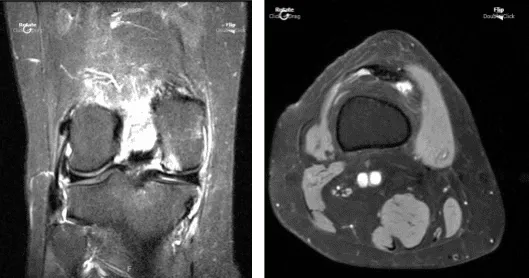

El paciente volvió a nuestra consulta una semana después de la visita inicial. Presenté radiografías bilaterales. La rodilla izquierda muestra pequeños defectos cartílagos de grosor total en la parte medial con el aspecto inferior de las facetas rotulianas laterales y edema subyacente parcheado de médula ósea subcondral.

Defectos de cartílago de pequeño espesor parcial en la cara troclear medial. Pérdida de cartílago de pequeño espesor parcial, aspecto central del cóndilo femoral medial con pequeño edema subcondral débil de médula ósea subyacente. Derrame articular pequeño y ligamentos cruzados y colaterales intactos.

La resonancia magnética de la rodilla derecha mostró la siguiente impresión: defecto cartílago de grosor total, aspecto inferior de la faceta rotuliana lateral y pequeñas fisuras cartílagoas de grosor total de la faceta patuliana medial con edema subcondral de médula ósea.

Pequeña fisura cartílaga de grosor completo de la faceta troclear medial con pequeño edema subcondral subyacente. Defectos de cartílago de grosor pequeño y completo en el aspecto central del cóndilo femoral medial con edema subyacente subcondral de médula ósea subcondral. Derrame articular pequeño a moderado. Quiste poplíteo traza.